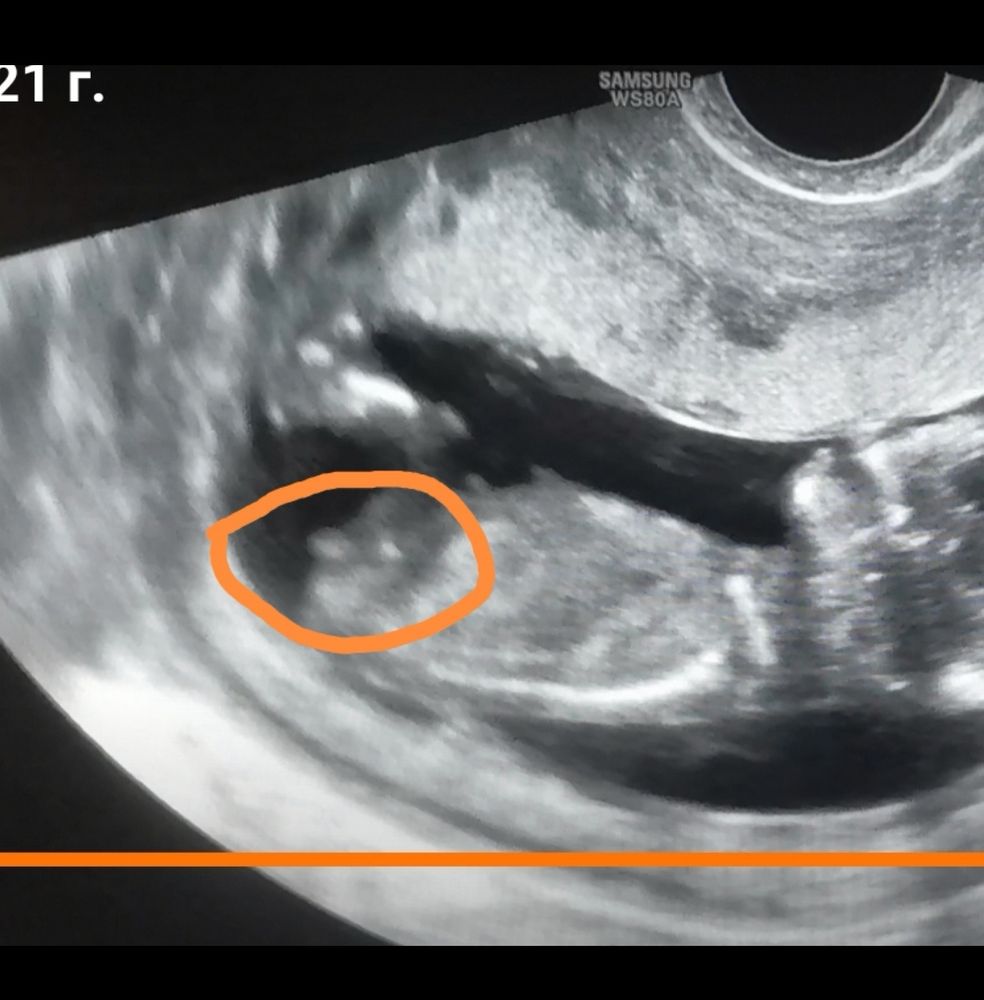

Бугорок не видно 🤷‍♀️ Изображение У нас чётко получилось на видео , сомнений не было

Не понятно…

Не видно половой бугорок...

Не видно у вас, бугорок прикрыл ножкой. можно только погадать)